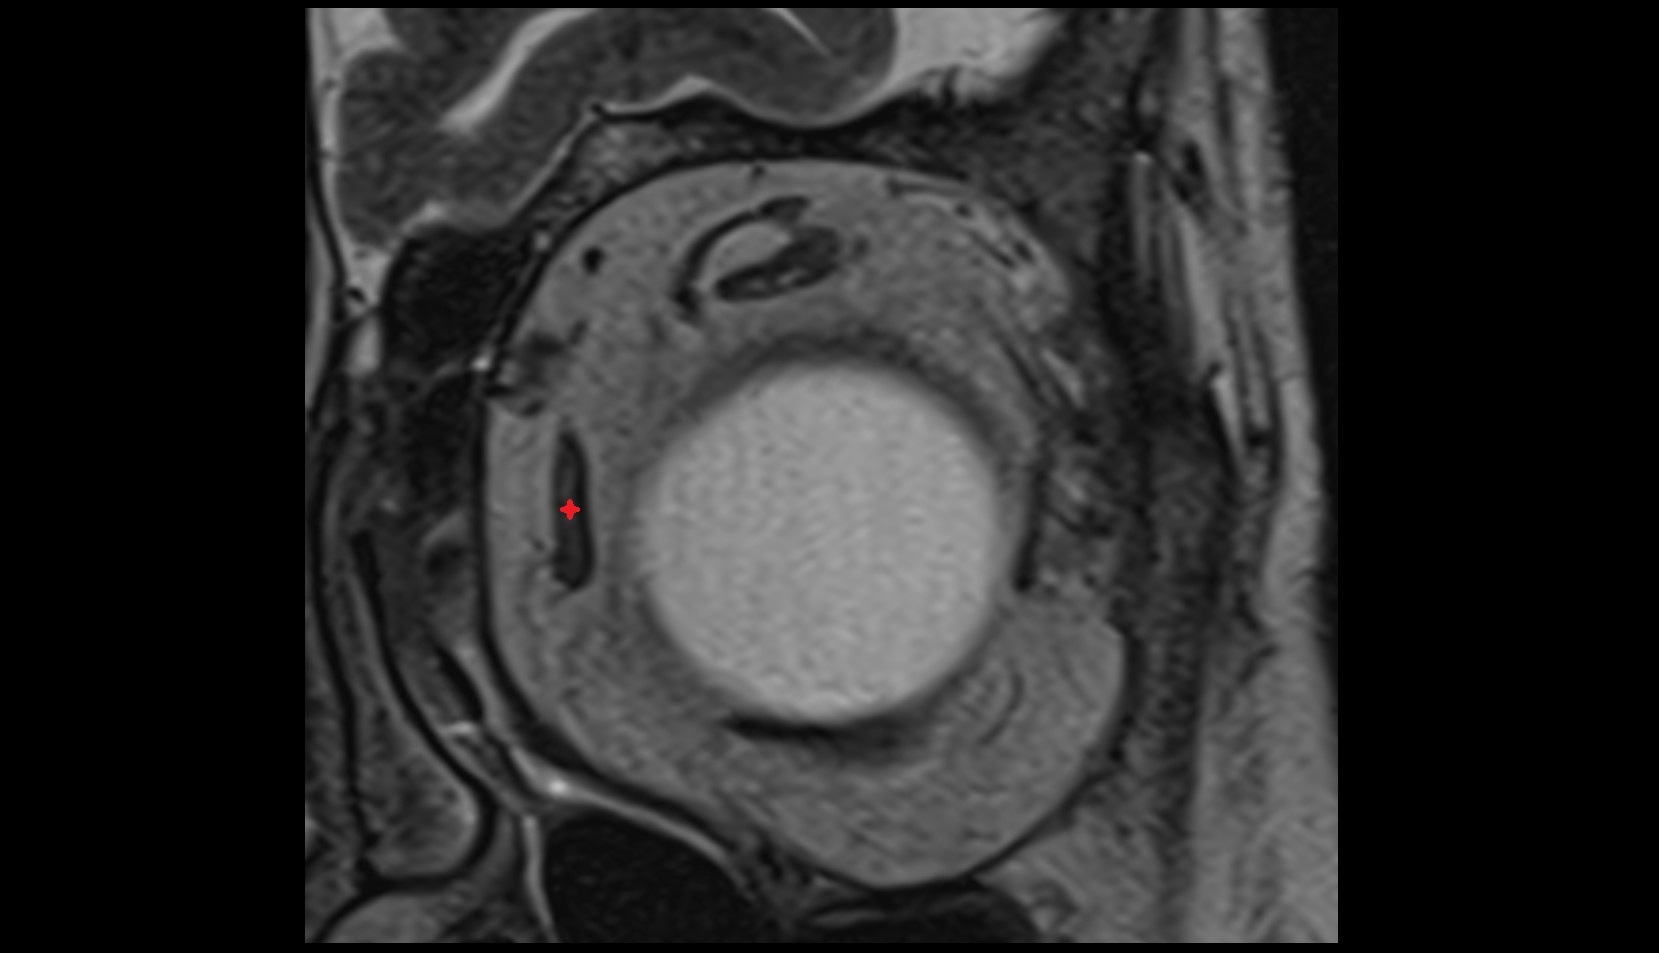

- Uterus

- Body of uterus

- Fundus of uterus

- Cervix of uterus

- Isthmus of uterus

- Endometrium of uterus

- Myometrium of uterus

- Perimetrium of uterus

- Junctional zone of uterus